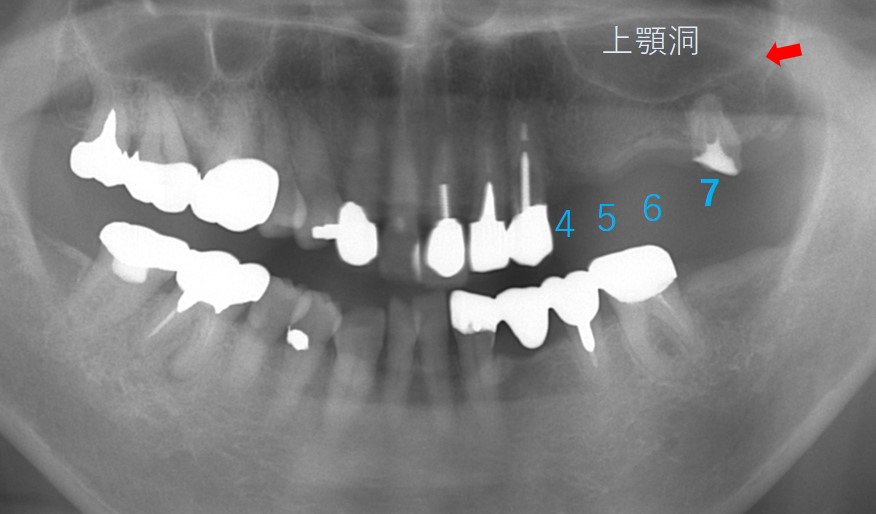

70歳女性です。4番が歯根破折(歯の根が折れる)ため抜歯適応となりました。4、5、6と3本の歯がなくなってしまうためブリッジはできません。また、入れ歯にも抵抗があるためインプラント治療を計画することとしました。

インプラントは、4番と6番に計2本埋入予定。4番は9mmの長さ、6番は上顎洞があるためショートインプラント(6mm)を予定しました。

4番と6番にインプラントを埋入した直後の写真です。